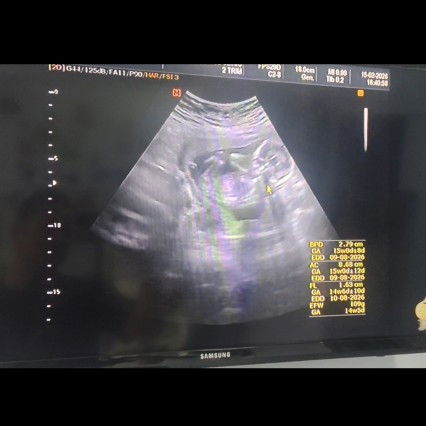

ภาพอัลตร้าซาวด์

แม่ๆคิดว่าผู้ชายหรือผู้หญิงค่ะ ช่วยดูไห้หน่อยค่าาา🙏🏻🙏🏻